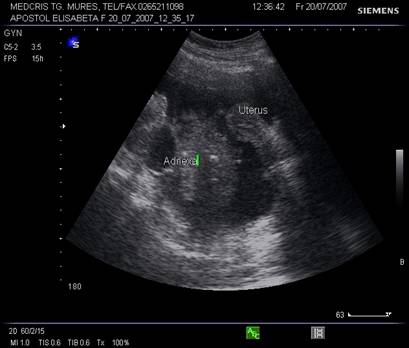

Ovarele. Sectiunea longitudinala directa, spre peretele lateral pelvin, la ecografia transvaginala, pune in evidenta ovarele cu forma elipsoidala. Acestea au structura ecografica relativ slab ecogena, in apropierea si sub vasele iliace.[5]

La pacientele care nu consuma contraceptive hormonale orale se pot identifica usor foliculii selectati preovulator sau corpul galben.

Fig. Nr. 360.Ovar sub vasele iliace , in ziua a XXI a de ciclu menstrual